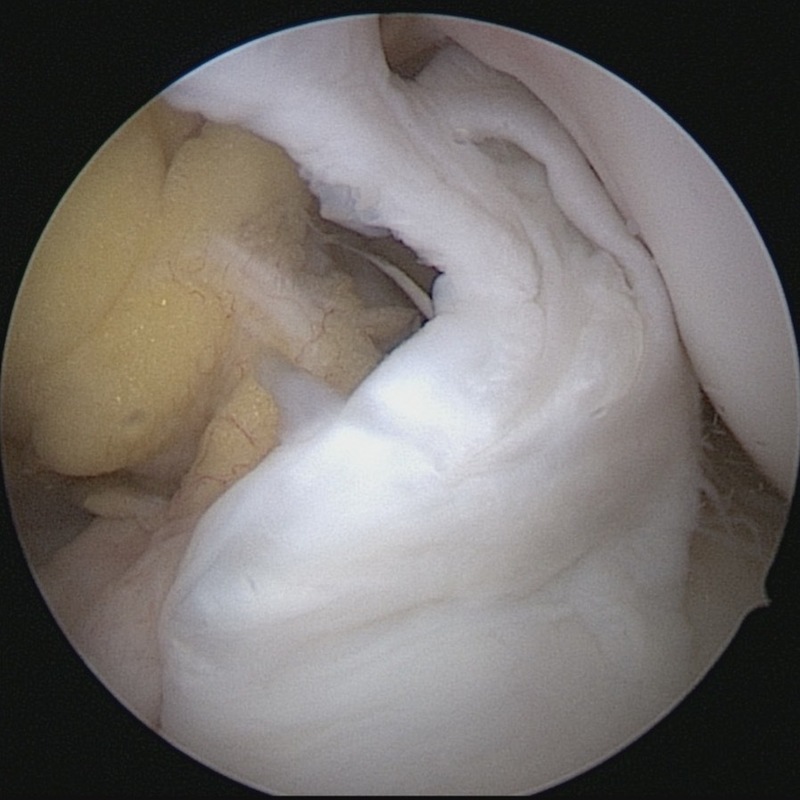

関節鏡では膝関節内に太くしっかりした靭帯としてみることができます。前十字靭帯が損傷してしまうと緊張がなくなり垂れ下がるようになることもあります。